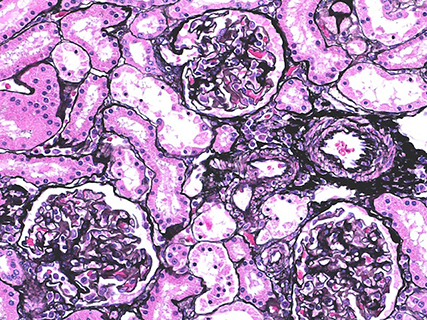

PAM staining (marmoset kidney)